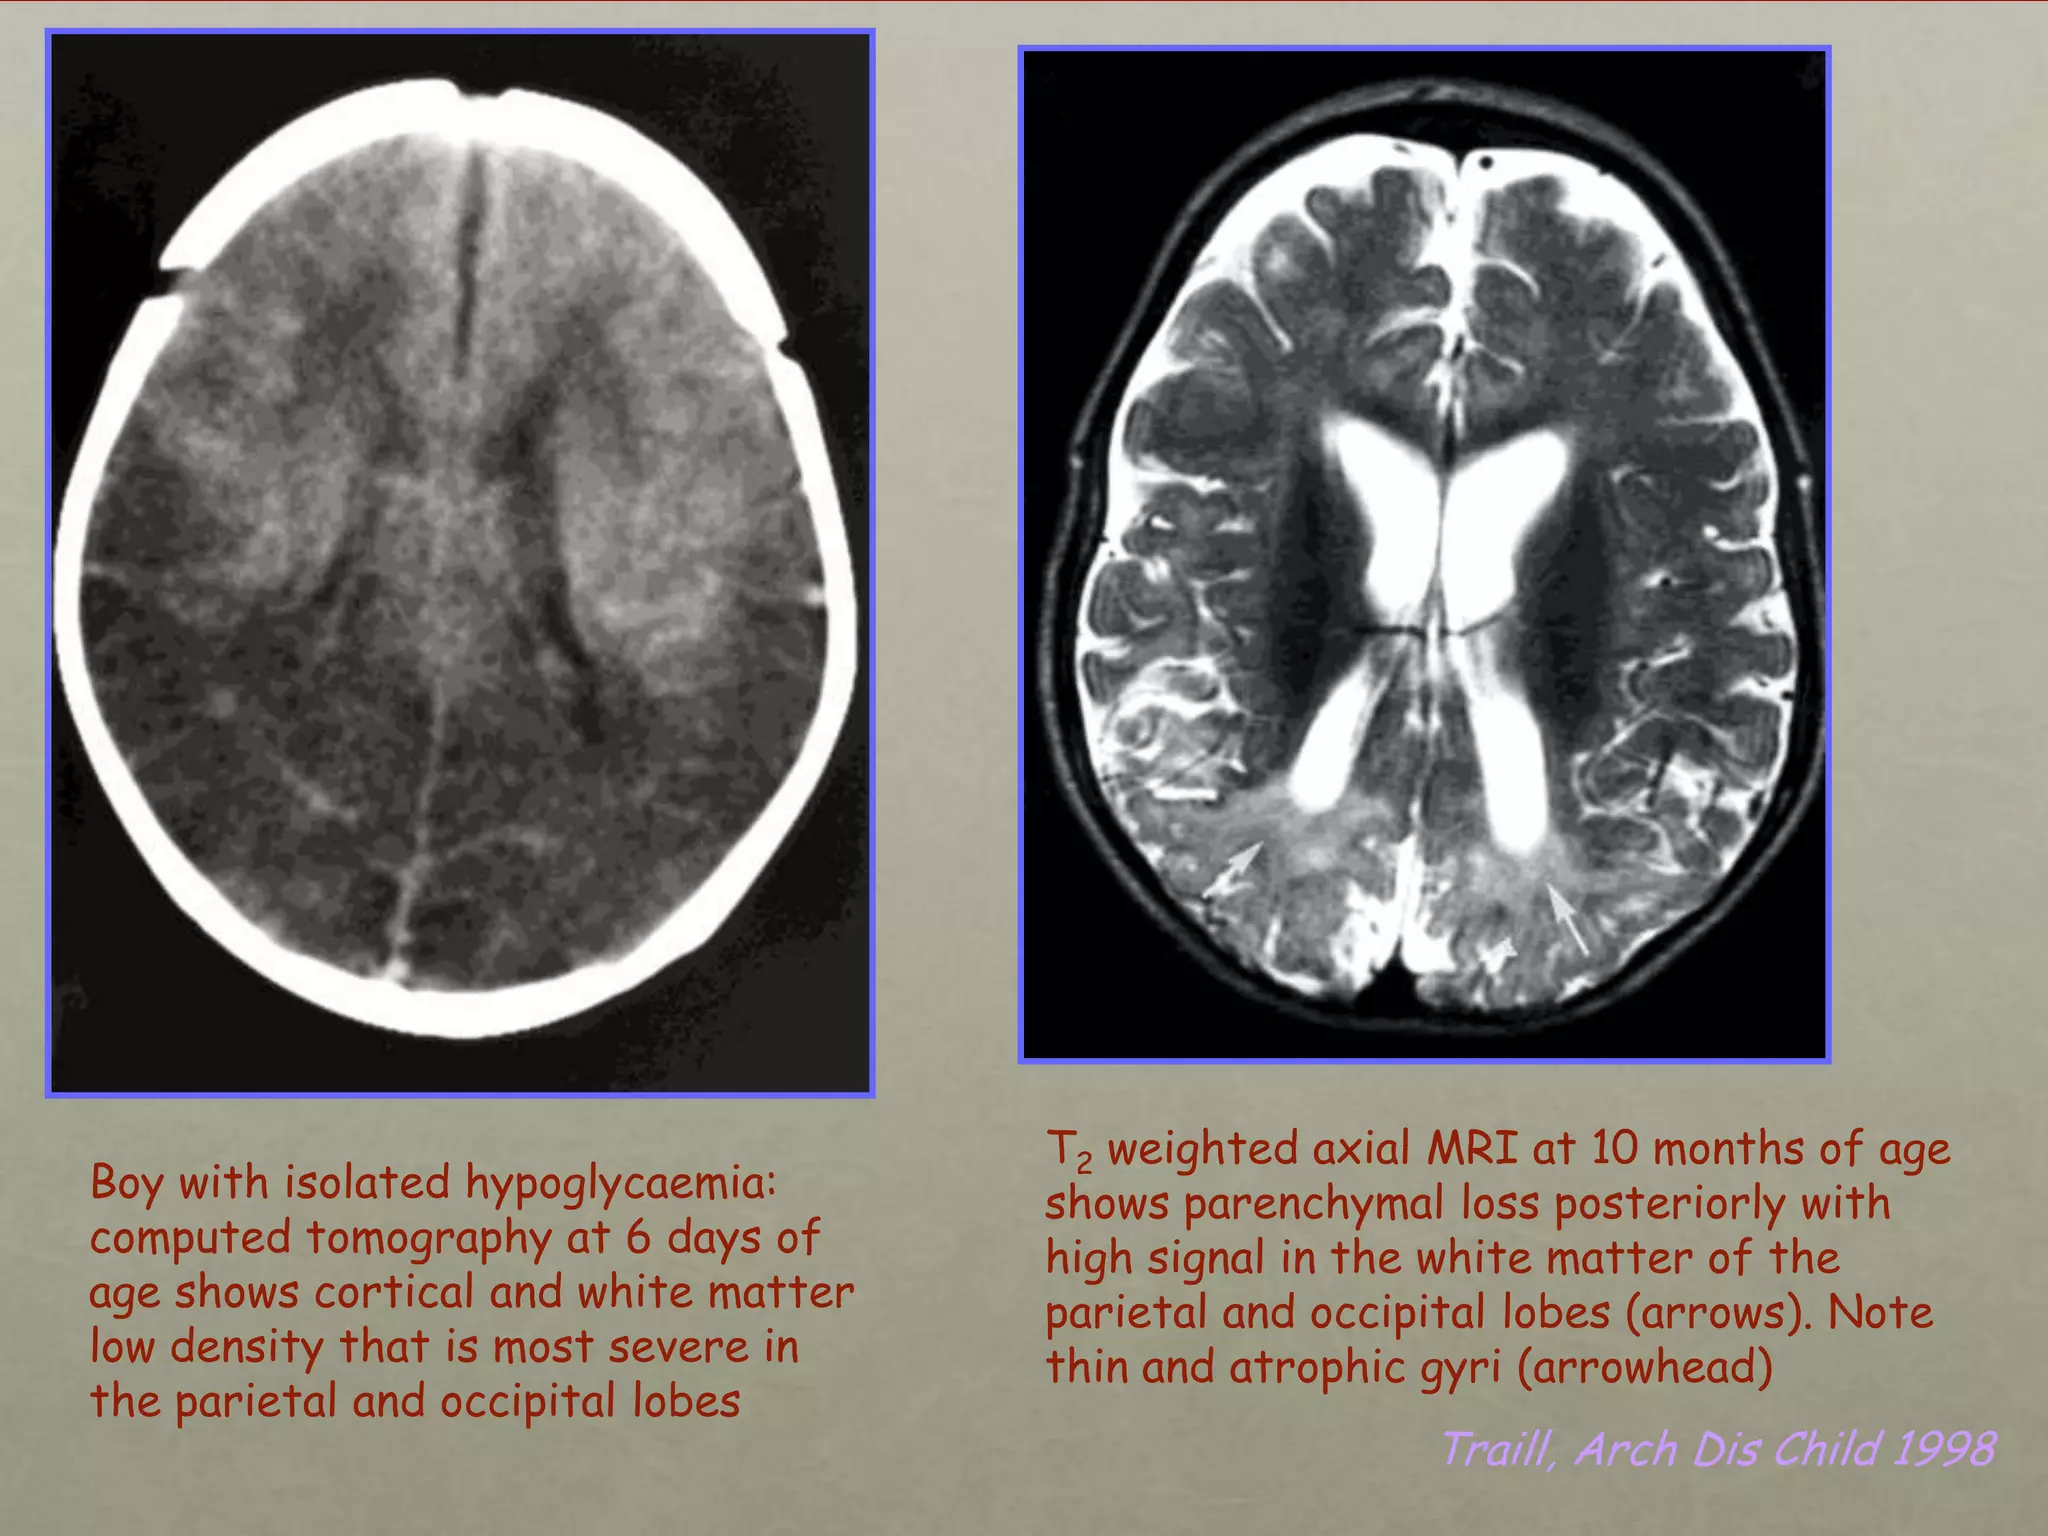

Boy with isolated hypoglycaemia:

computed tomography at 6 days of

age shows cortical and white matter

low density that is most severe in

the parietal and occipital lobes

T2 weighted axial MRI at 10 months of age

shows parenchymal loss posteriorly with

high signal in the white matter of the

parietal and occipital lobes (arrows). Note

thin and atrophic gyri (arrowhead)

Traill, Arch Dis Child 1998

Boy with isolatedhypoglycaemia: computed tomography at 6 days of age shows cortical and white matter low density that is most severe in the parietal and occipital lobes T2 weighted axial MRI at 10 months of age shows parenchymal loss posteriorly with high signal in the white matter of the parietal and occipital lobes (arrows). Note thin and atrophic gyri (arrowhead) Traill, Arch Dis Child 1998